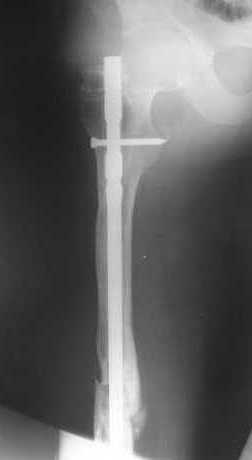

В приложении пример, как их использовали после остеотомии бедра по поводу сросшегося с вальгусом перелома, чтобы не дать гвоздю уйти во внутренний мыщелок.

Да, действительно красивый клинический пример: виден вальгус до операции и последующая коррекция углового смещения на "полярах". Я так понимаю, что в вашей клинике есть возможность использовать различные фиксаторы. Почему не использовали DFN? Спицы какие используете? Киршнера или Илизаровские? С виду очень тонкие...